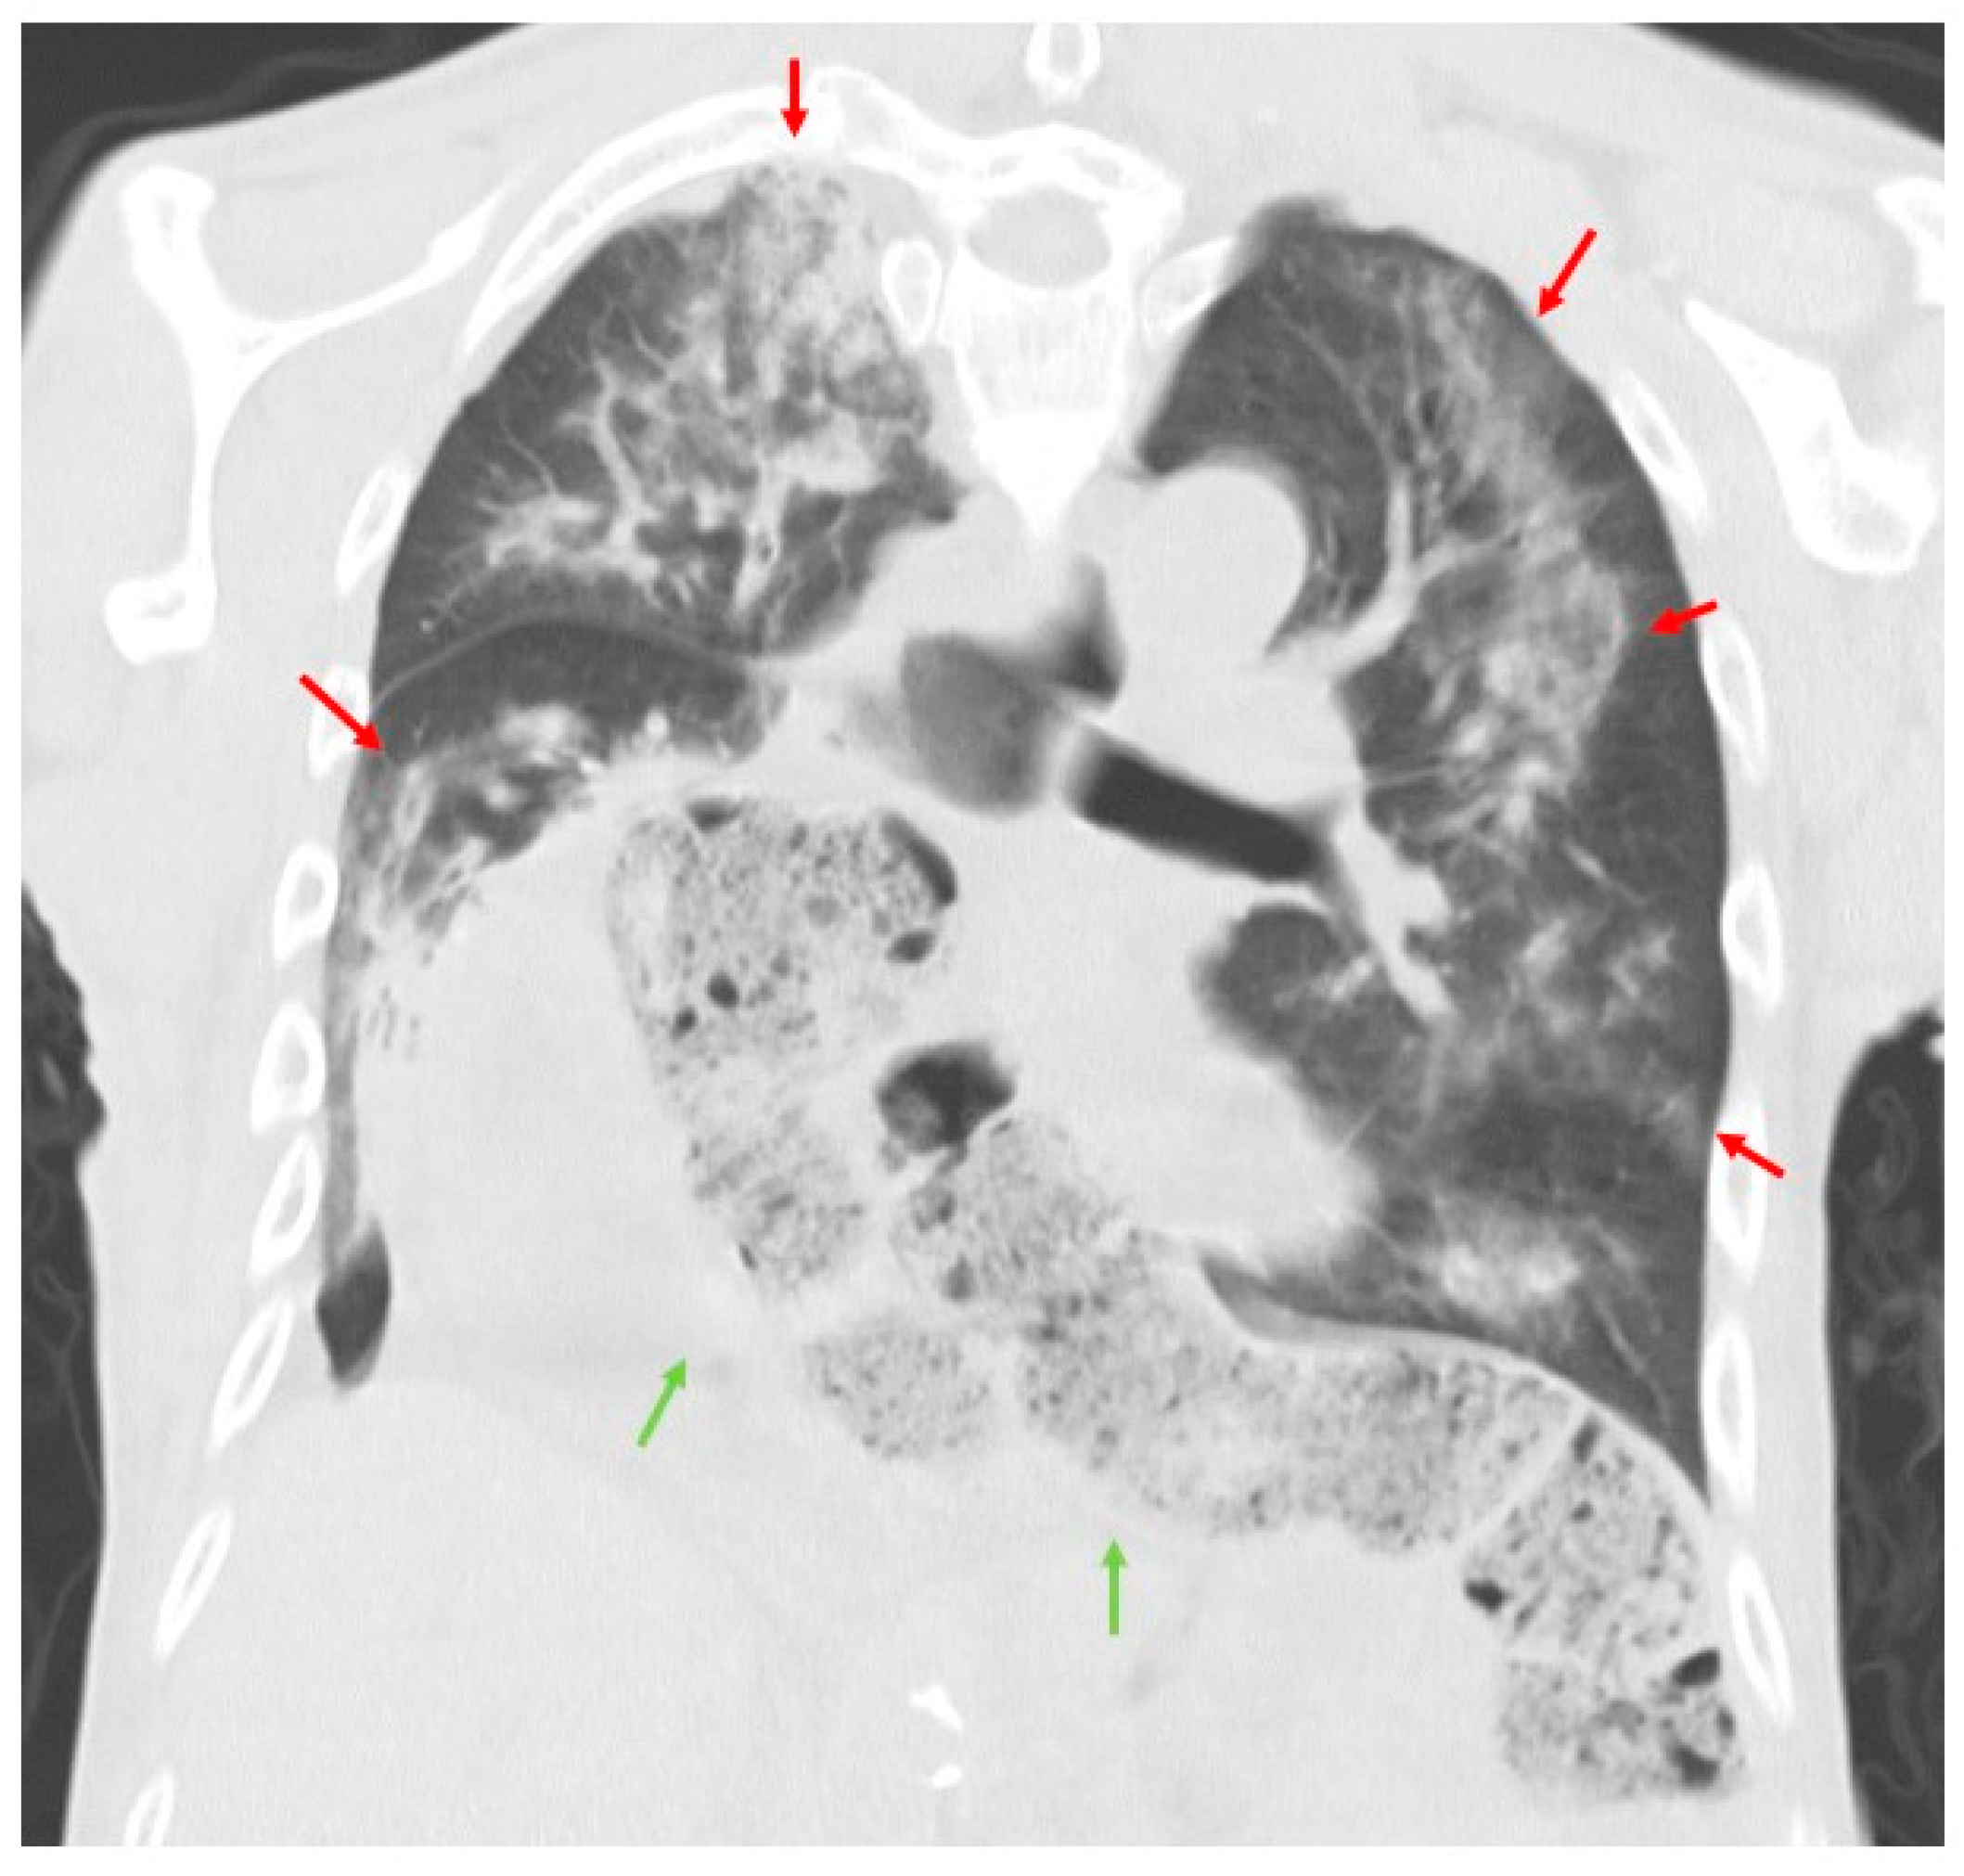

2. Case Presentation